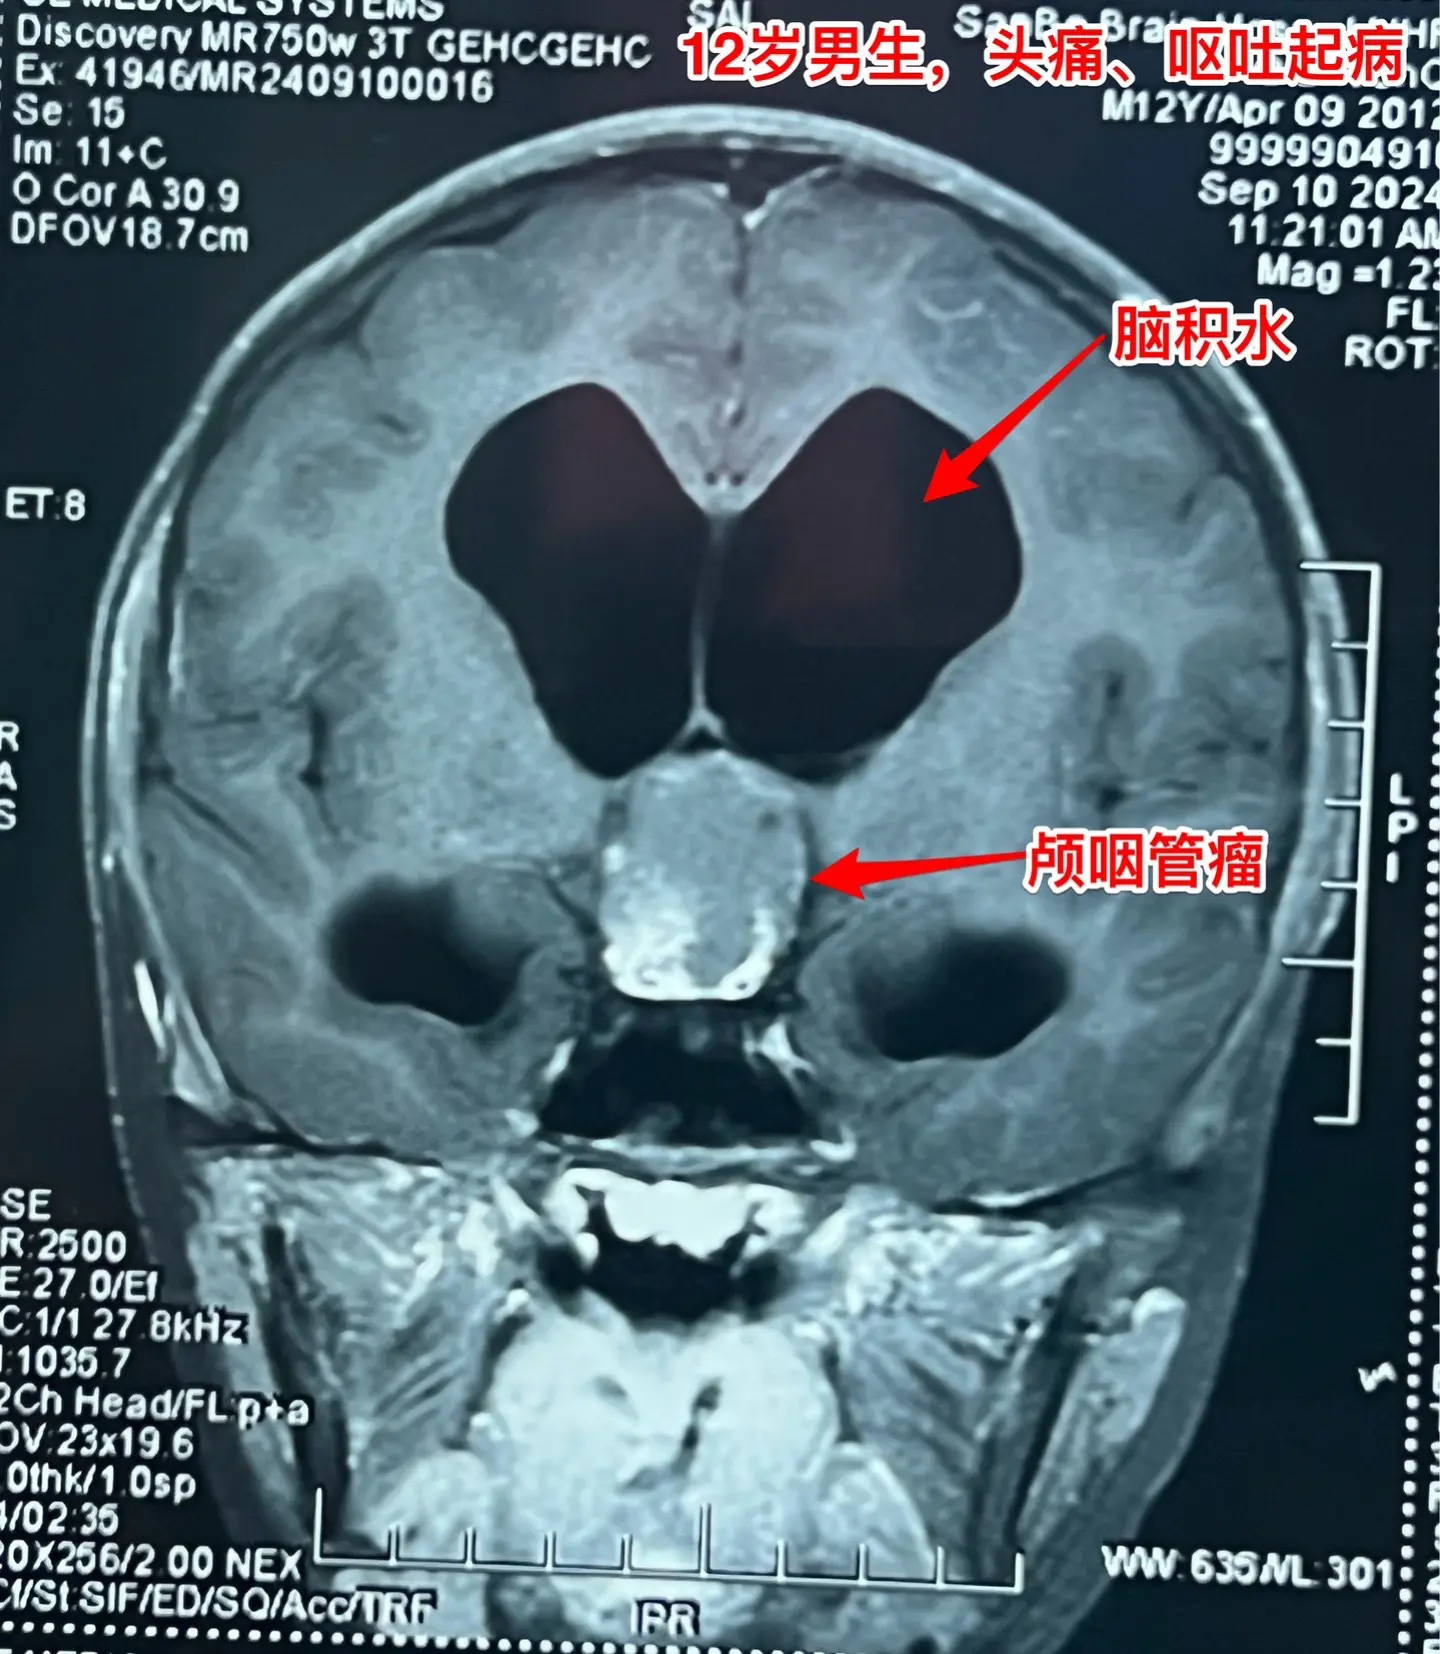

12岁南京男孩子头痛、呕吐。平时感觉身体很好,9月7日因头痛、呕吐到医院检查发现脑部长了颅咽管瘤,并且有脑积水。 9月9日到我院住院。住院时头痛、呕吐症状减轻了。复查磁共振显示颅咽管瘤的形态稍有变化,脑积水似乎有减轻。测视力发现他的视力有下降。这个颅咽管瘤生长的时间预计有两年时间,患儿症状不严重,最终因脑积水出现头痛、呕吐症状才发病。仔细检查还是可以发现一些蛛丝马迹,比如视力下降。颅咽管瘤有时会自动变小,很可能是肿瘤囊破裂了。囊变小了,脑积水就减轻了,头痛、呕吐症状就减轻了。 9月19日行开颅手术,将颅咽管瘤完全切除。手术后患者感觉视力有好转。希望肿瘤永不复发。